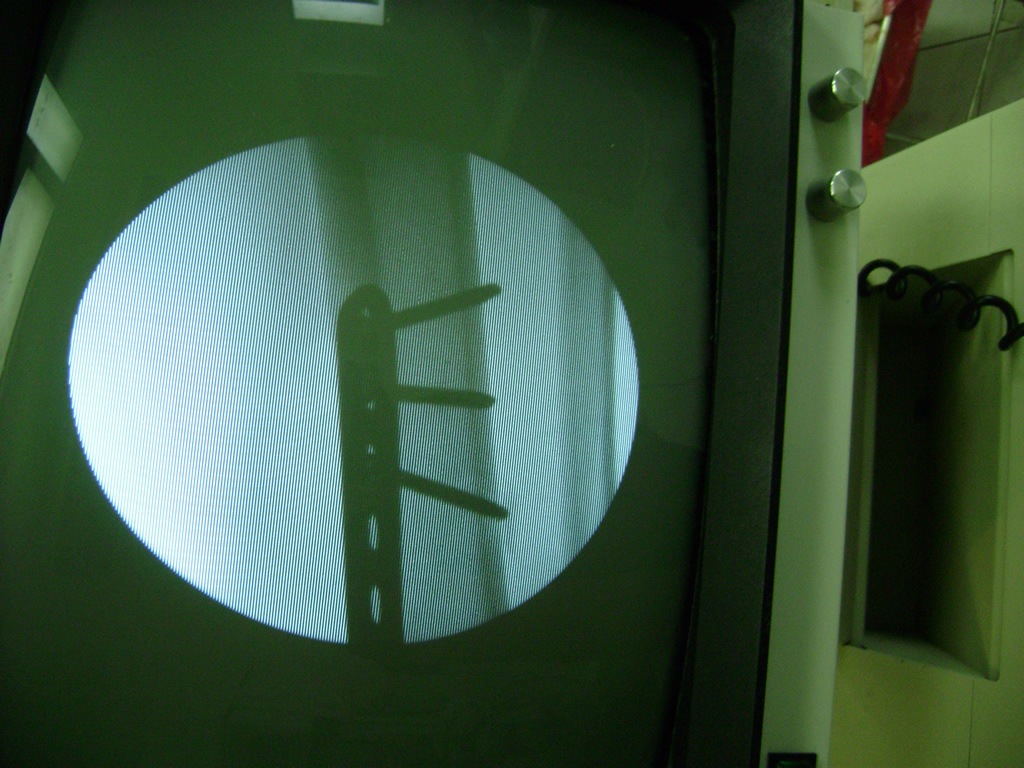

Debido a la fina cobertura de piel que recubre la tibia y el peroné, las fracturas generalmente son abiertas, es decir, el hueso roto rasga la piel, atravesándola. Las fracturas de tibia y peroné generalmente se producen por un fuerte impacto o torsión.